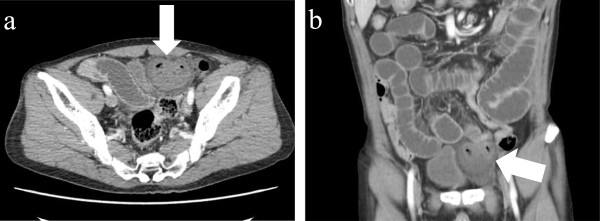

During a detailed interview, he said that he had noted a lump over his left groin for approximately 3 years that had initially been reducible by manipulation but had become progressively more difficult to reduce. Abdominal CT scan showed small bowel obstruction with a transition point in the left inguinal region (Figure 1). A segment of the intestine was entrapped within a hernial sac that was protruding into the pre-peritoneal space between the parietal peritoneum and anterior abdominal wall. The patient was diagnosed with a reduction en masse of an inguinal hernia and secondary mechanical small bowel obstruction.

Figure 1.

CT findings scan of the patient. Preoperative computed tomography findings of case showing small bowel obstruction with a transition point in the left inguinal groin. A segment of intestine is entrapped in a hernial sac protruding into the pre-peritoneal space; a horizonal view, b frontal view.